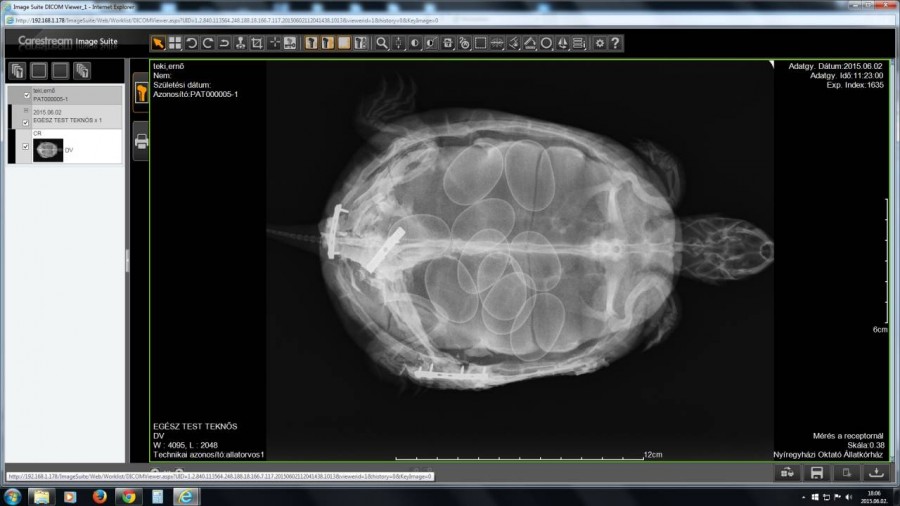

Viszont új meglepetéssel szolgált számunkra, ami az első röntgenfelvétele után vált biztossá. Sárában 13 tojás rejtőzött. A tojások lerakása nem probléma mentes az ő állapotában, de mindent megteszünk az ő és a tojások épségének érdekében

Már az első napokon túl vagyunk és sikeresen 3 tojást ,már kinyomott.